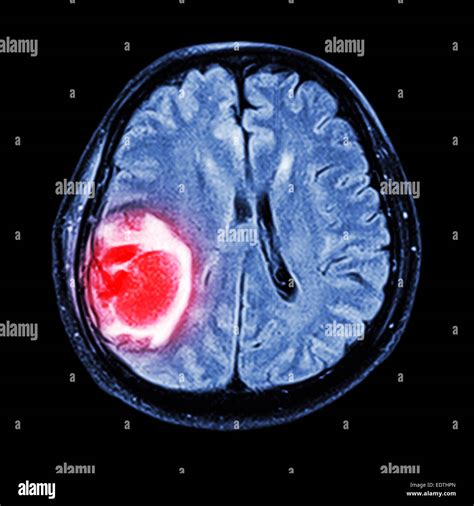

When a physician suspects an abnormality within the skull, a Brain Neoplasm MRI is the gold standard diagnostic tool used to visualize the intricate structures of the brain. Neoplasms, or abnormal tissue growths, can be benign or malignant, and magnetic resonance imaging (MRI) provides unparalleled detail to distinguish between these possibilities. By utilizing powerful magnets and radio waves rather than ionizing radiation, MRI technology produces high-resolution, cross-sectional images that allow radiologists and neurosurgeons to pinpoint the exact location, size, and characteristics of a potential tumor.

A standard Brain Neoplasm MRI protocol involves several different "sequences" or scan types. Each sequence is designed to highlight different biological features of the tissue. For example, T1-weighted images are excellent for anatomical detail, while T2-weighted and FLAIR (Fluid-Attenuated Inversion Recovery) images are highly sensitive to identifying edema or inflammation around a mass.

To improve the diagnostic accuracy, doctors often use a gadolinium-based contrast agent. When injected intravenously, this contrast material accumulates in areas where the blood-brain barrier is compromised, which is typical in many types of neoplasms. This "enhancement" helps doctors clearly delineate the tumor from healthy brain tissue.

• Diffusion-Weighted Imaging (DWI): Measures the movement of water molecules to help distinguish between different types of tumors or identify abscesses.